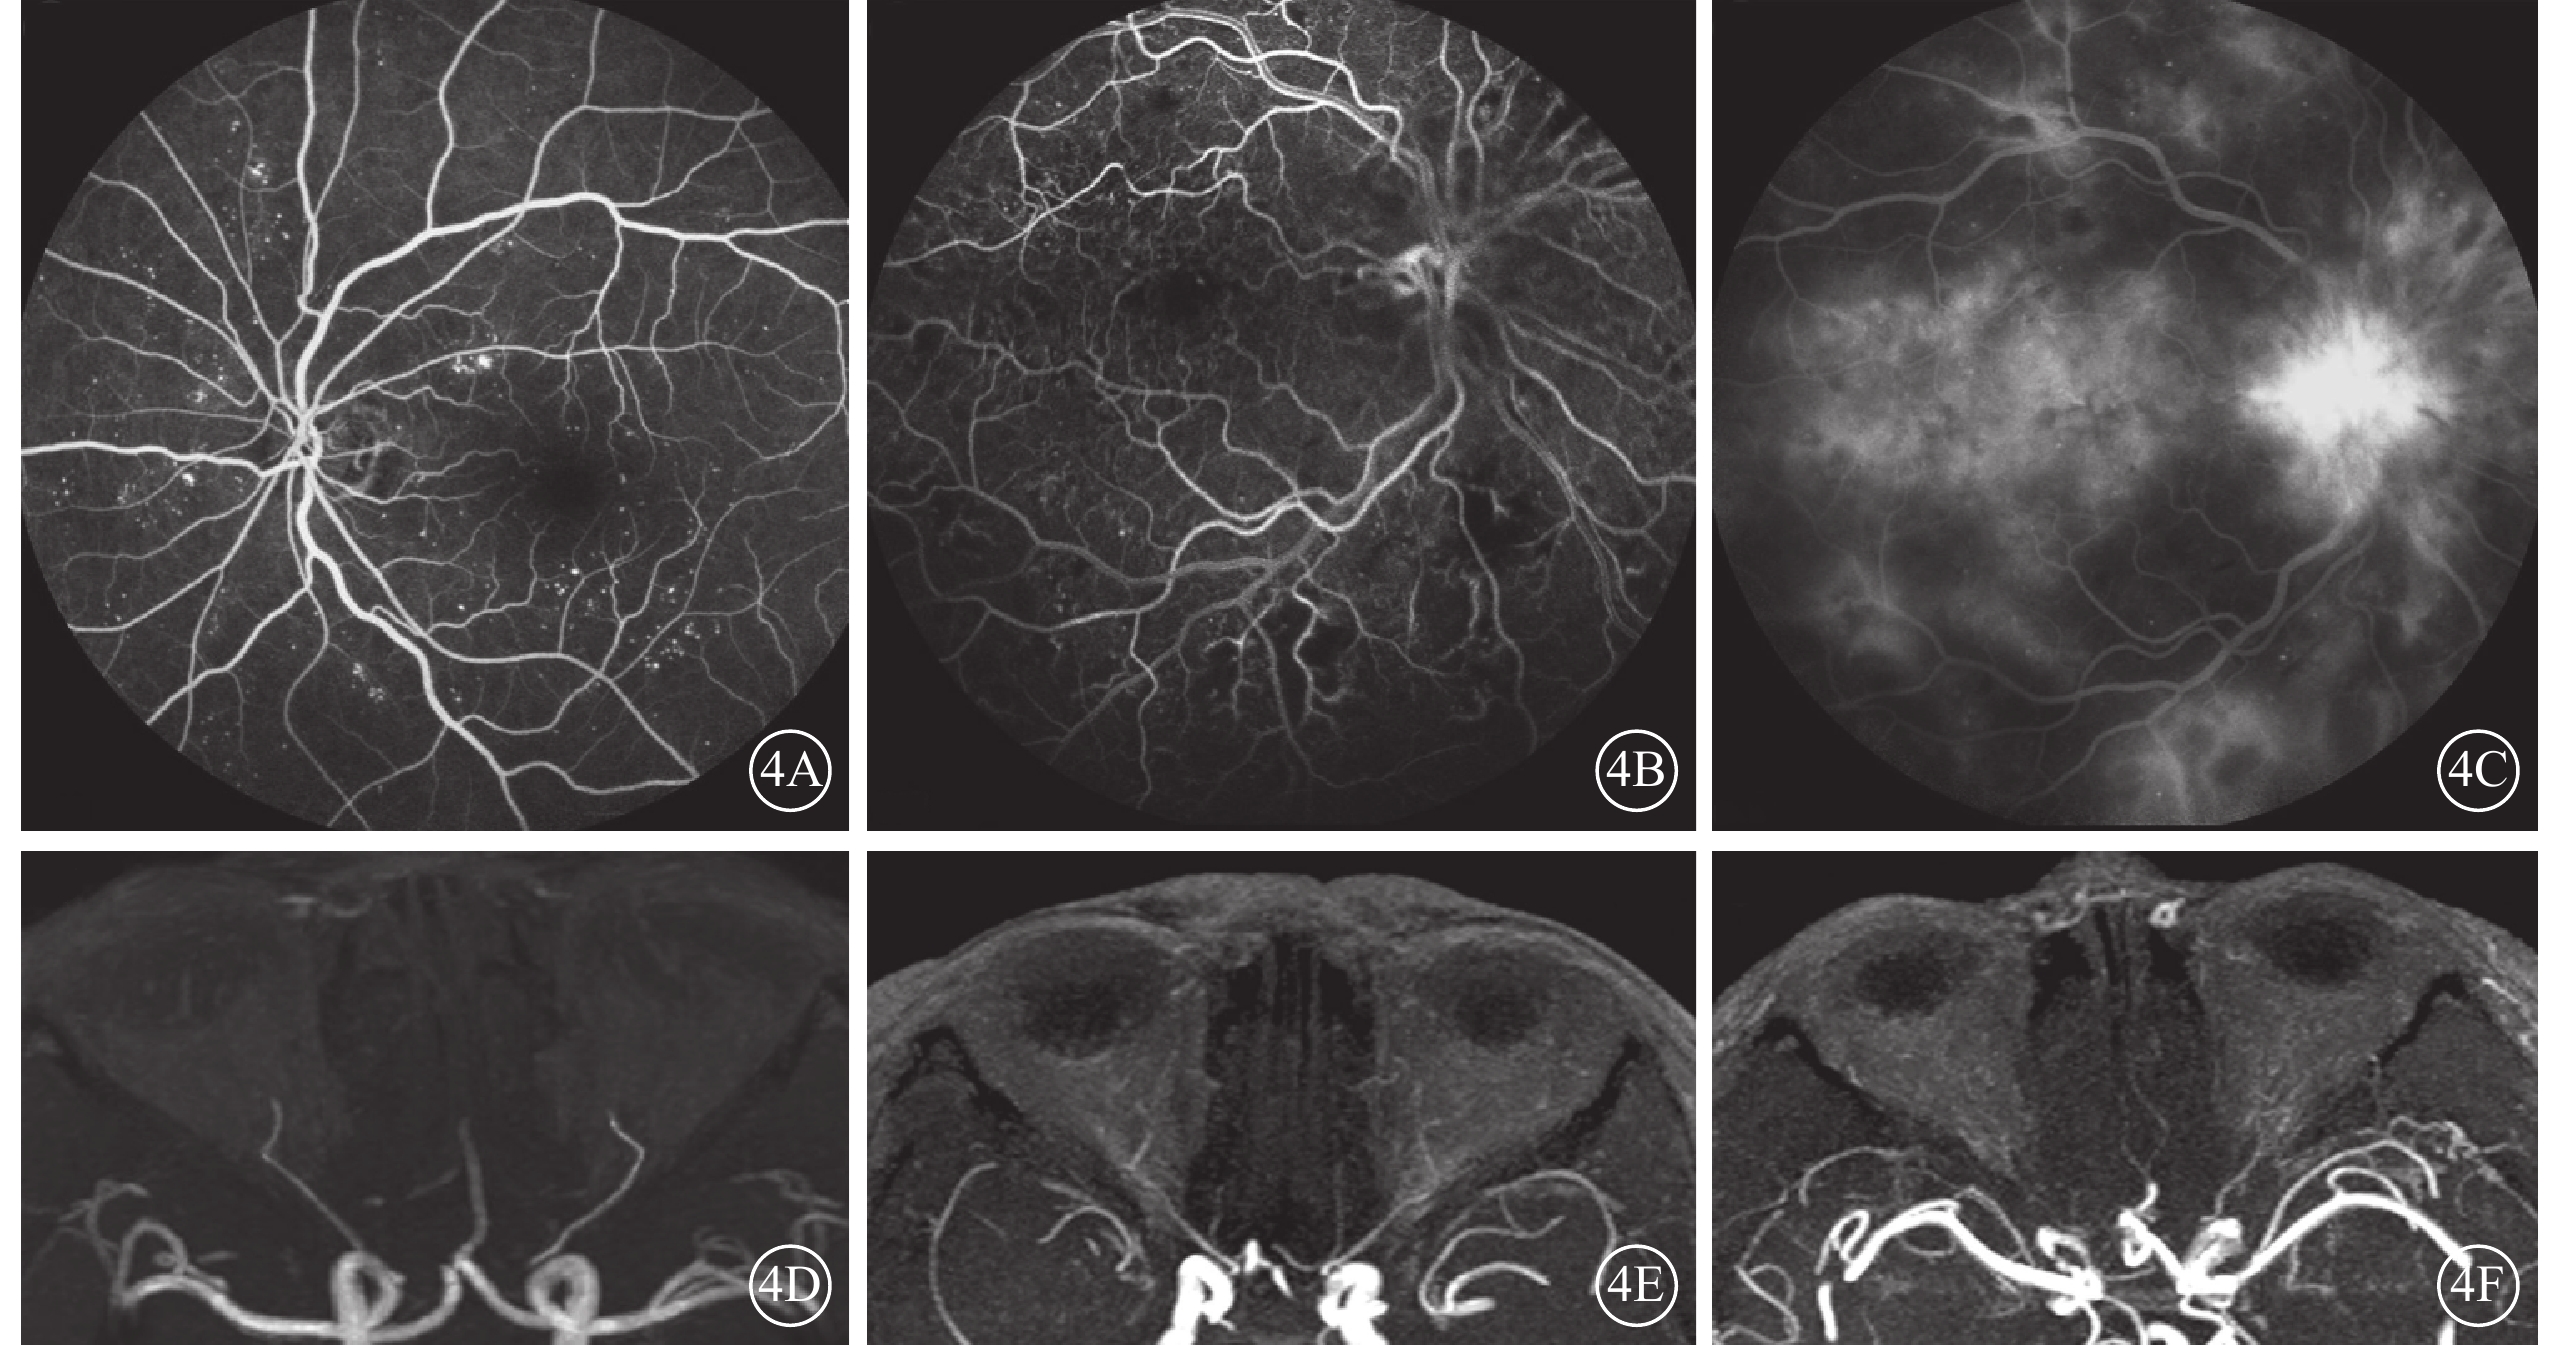

DR組72只眼中,FFA無明顯病變期、背景期、增生前期、增生期分別為8、12、22、30只眼。 相關性分析結果顯示,DR組眼動脈MRA分級與FFA分期呈顯著相關性(r=0.405,P=0.000);分級比較顯示DR組FFA分期越重,眼動脈MRA顯影越差(表2,圖4)。

圖4

DR患者FFA、MRA像。4A~4C. FFA像,分別為背景期、增生前期、增生期;4D~4F. 4A~4C同側眼動脈MRA像,分別為0級、Ⅰ級、Ⅱ級。FFA分期越重,眼動脈MRA顯影越差

圖4

DR患者FFA、MRA像。4A~4C. FFA像,分別為背景期、增生前期、增生期;4D~4F. 4A~4C同側眼動脈MRA像,分別為0級、Ⅰ級、Ⅱ級。FFA分期越重,眼動脈MRA顯影越差

DR組72只眼中,FFA無明顯病變期、背景期、增生前期、增生期分別為8、12、22、30只眼。 相關性分析結果顯示,DR組眼動脈MRA分級與FFA分期呈顯著相關性(r=0.405,P=0.000);分級比較顯示DR組FFA分期越重,眼動脈MRA顯影越差(表2,圖4)。

圖4

DR患者FFA、MRA像。4A~4C. FFA像,分別為背景期、增生前期、增生期;4D~4F. 4A~4C同側眼動脈MRA像,分別為0級、Ⅰ級、Ⅱ級。FFA分期越重,眼動脈MRA顯影越差

圖4

DR患者FFA、MRA像。4A~4C. FFA像,分別為背景期、增生前期、增生期;4D~4F. 4A~4C同側眼動脈MRA像,分別為0級、Ⅰ級、Ⅱ級。FFA分期越重,眼動脈MRA顯影越差